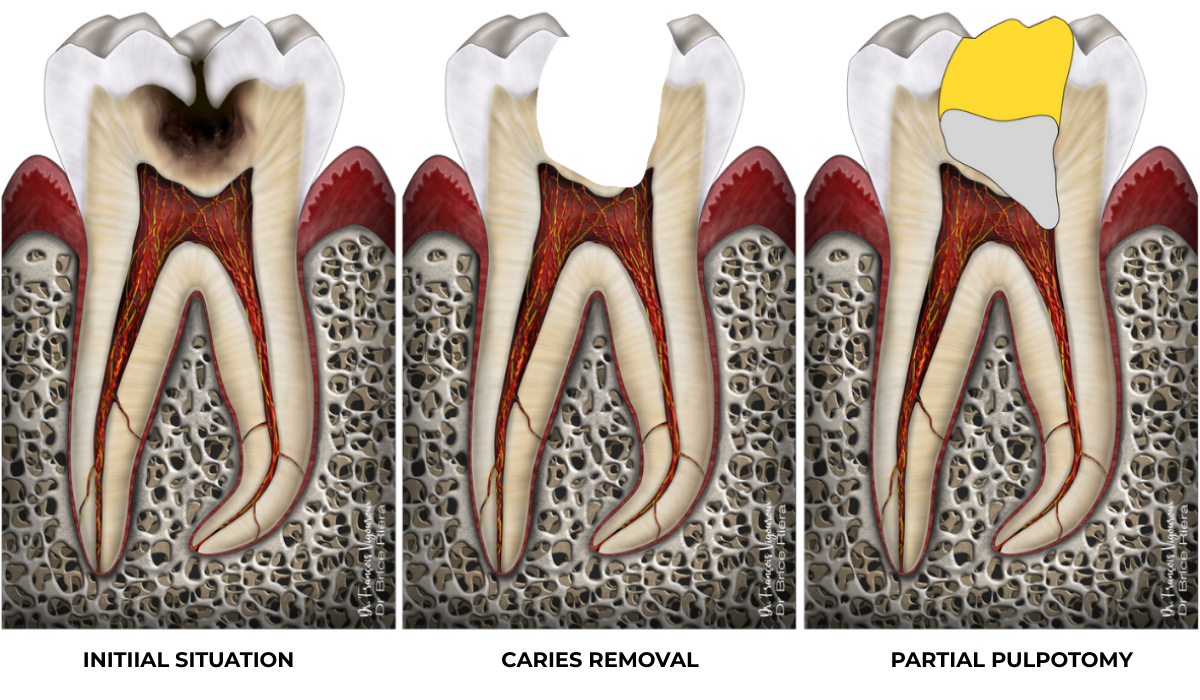

Coronal pulpotomy

Whether during diagnosis or during the procedure itself, it is possible that the coronal pulp cannot be preserved. The coronal pulp is the pulp located in the pulp chamber (left-hand diagram in transparent red).

On the right, in yellow: coronal restorative material / in grey: bioactive biomaterial (such as bioceramic cement)

Full pulpotomy: 91.3% success rate